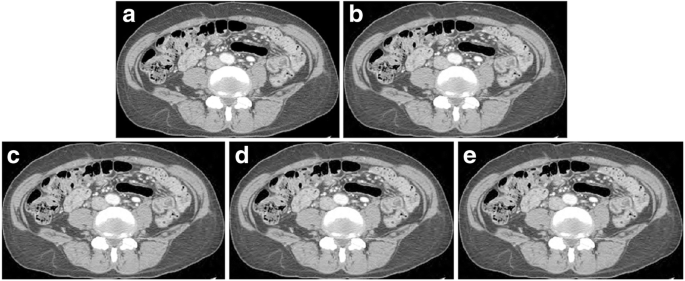

JPEG 2000 compressed CT images in transverse abdominal view of a 78-year-old female. (a) the original image. (b) the compressed image by a radiologist. (compression ratio 8.6:1.) The compressed images using (c) the MLR model (8.8,1), (d) the PSNR (9.5,1), and (e) the HDRVDP (9.3,1) respectively. Window width and level are set to 400 and 20 HU. Since the images are generated by visually lossless compression methods, all the images are indistinguishable from the original image